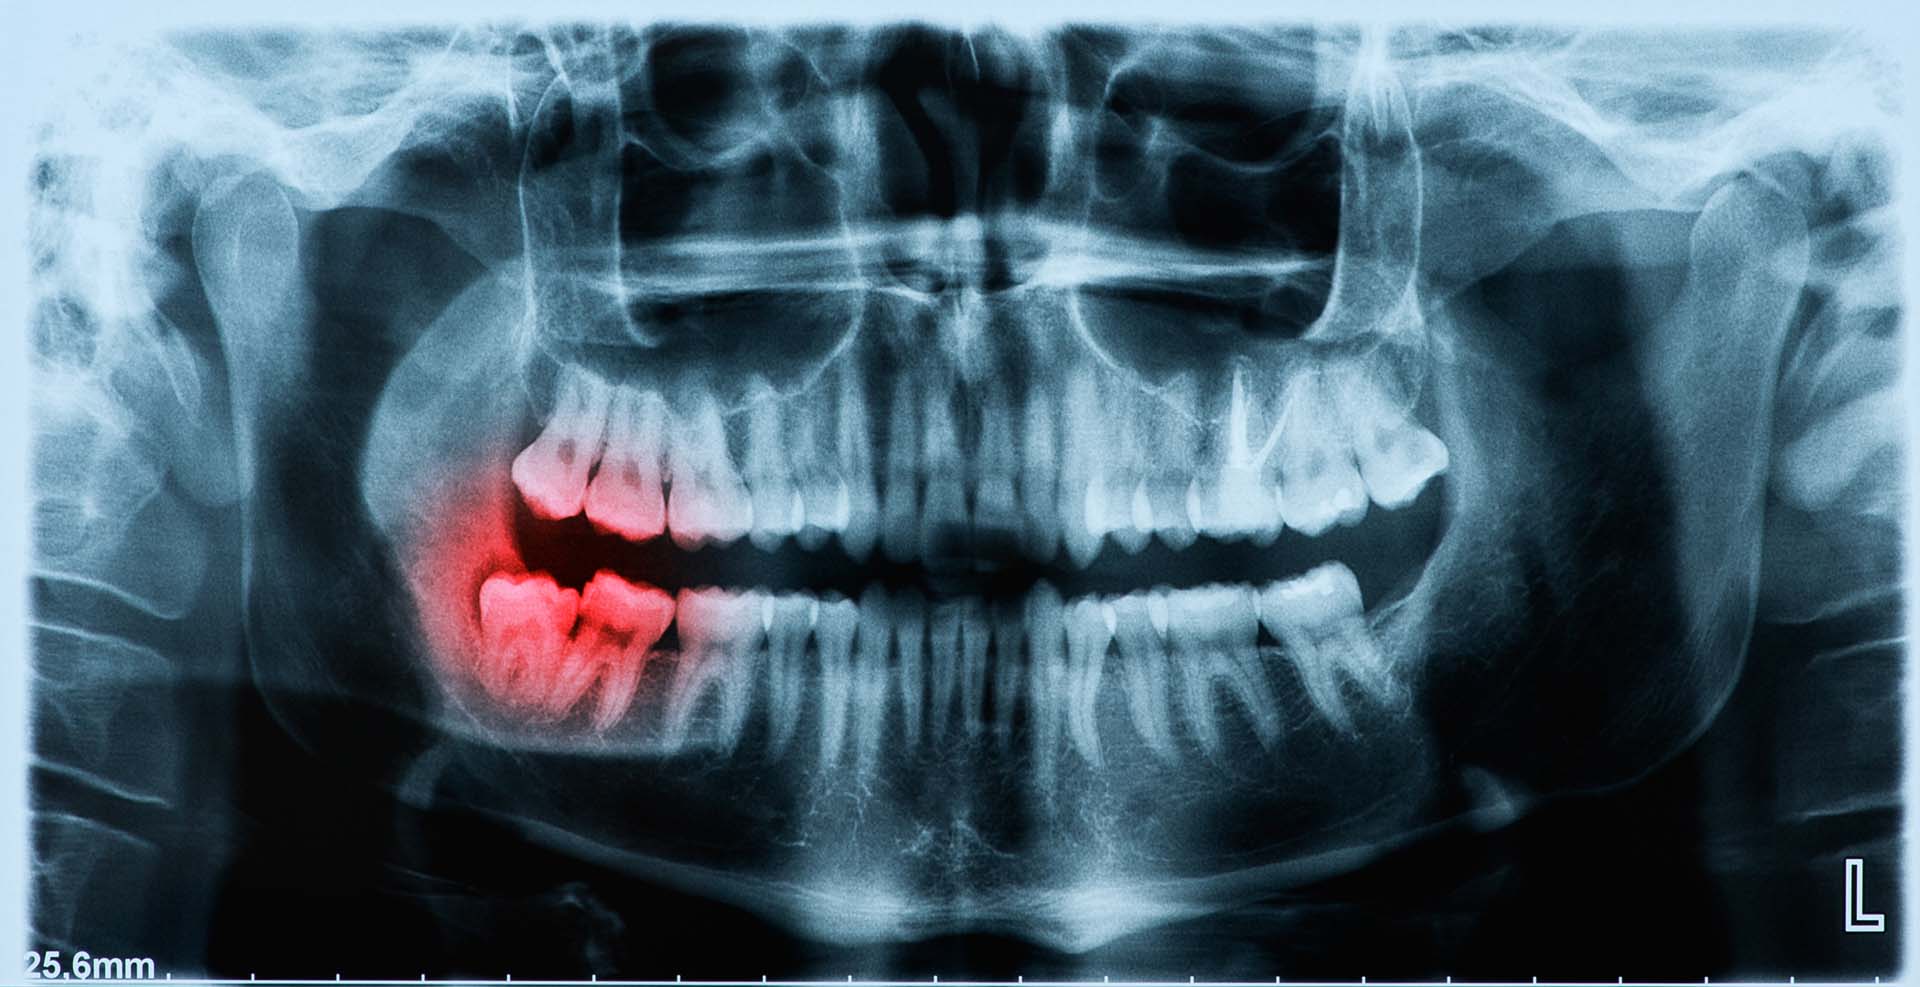

- Consultation and Imaging

We begin with a comprehensive dental exam, including digital x-rays or 3D imaging, to assess the number, location, and angle of the wisdom teeth. - Sedation and Anesthesia Options

We evaluate your wisdom teeth using digital x-rays and check for signs of impaction, infection, or lack of space. Even if you don’t feel pain, proactive removal may be recommended to prevent future problems.